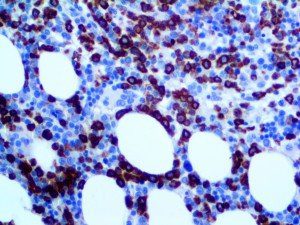

It is the ICU physician who is most likely to witness one of the deadliest manifestations of the abnormal immunological response, the cytokine storm syndrome (CSS). This response is also referred to by some as the cytokine release syndrome (CRS). CSS is characterized by continuous activation and expansion of macrophage and lymphocyte populations, which secrete large amounts of cytokines, causing the cytokine storm. This massive cytokine release is akin to hemophagocytic lymphohistiocytosis (HLH) disease, a syndrome characterized by initial unchecked and persistent activation of cytotoxic T lymphocytes and NK cells.

Clinical and laboratory manifestations of HLH include fever, enlarged liver and/or spleen, neurologic dysfunction, coagulopathy, liver dysfunction, cytopenias (i.e., low levels of erythrocytes, leukocytes, and/or platelets), hypertriglyceridemia, hyperferritinemia, hemophagocytosis, and eventually diminished NK cell activity as the immune system becomes progressively paralyzed. HLH can be familial (primary HLH) or secondary to another disease process (sHLH), such as rheumatic disease, in which it is referred to as macrophage activation syndrome (MAS, characterized by elevated ferritin).